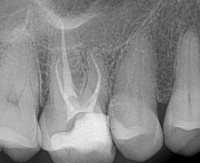

Re-treatment was performed, and the MM canal was identified, instrumented and obturated. The final radiographs show that the lateral lesion corresponds with the MM canal and its lateral exit point (Fig 3 and 4).

Procodile Q™ files were helpful in instrumenting all 5 canals—and for removing gutta percha during the re-treatment of the previously obturated canals—due to their reciprocating motion when they meet resistance!